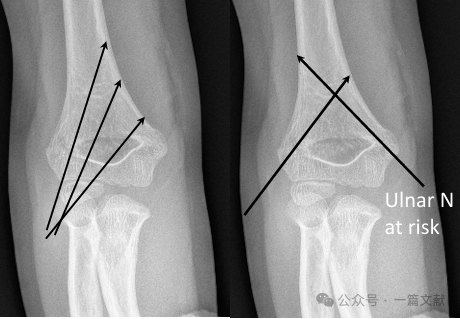

K-Wire Fixation Techniques:

* Lateral-Only Pinning:

* Most commonly used technique.

* Can utilize 2 or 3 laterally placed K-wires.

* Cross Pinning (Medial & Lateral):

* Provides biomechanical stability.

* Carries a risk of iatrogenic ulnar nerve injury.

* Ideal Pin Placement Requirements: Use 1.5-2 mm K-wires. Pins should engage the medial and lateral columns with a divergent pattern. Greater separation between pins increases stability. As shown in the figure, pin configurations for Type 2A, 2B, and 3 fractures.

* Achieve wide separation at the fracture site.

* Pins should follow the metaphyseal flare to capture the lateral column.

* Laterally placed pins can be used to capture the medial column.

* Pin tips should engage the distal fragment just proximal to the fracture line.

* A third pin can be added between the two main pins for additional stability.